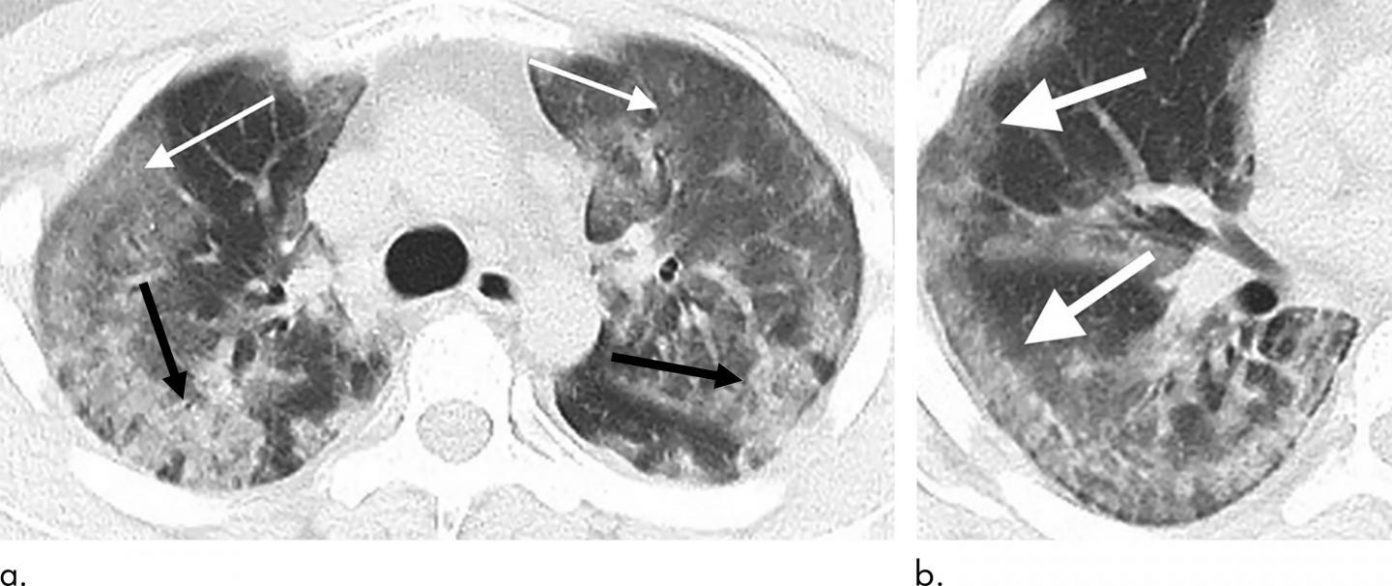

Поражение легких является одним из основных симптомов коронавируса (COVID-19). В данной статье представлены фото рентгеновских снимков, которые позволяют визуально оценить состояние легких при этом заболевании.

Матовое стекло коронавирус кт

Фото рентгеновских снимков поражения легких при COVID-19

На фотографиях рентгеновских снимков видно, как вирус воздействует на легочную ткань. Характерные признаки поражения легких включают пятна, инфильтраты и наличие жидкости внутри легочных альвеол.

Фото рентгеновских снимков помогают врачам и специалистам визуально определить степень поражения легких и принять соответствующие меры лечения и поддержки пациента.